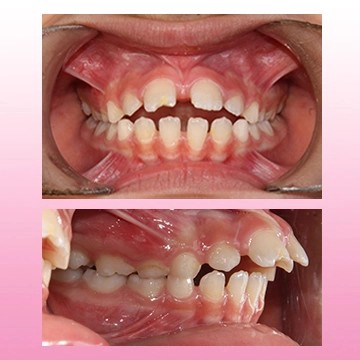

نمونه درمان ارتودنسی کودکان

تو سن 12 سالگی با مشکل بیرون زدگی فک بالا و عقب بودن فک پایین مراجعه کرد. تحت درمان فانکشنال، مشکل فک کاملا درمان شد. بعد اون با ارتودنسی ثابت درمانش تکمیل شد.